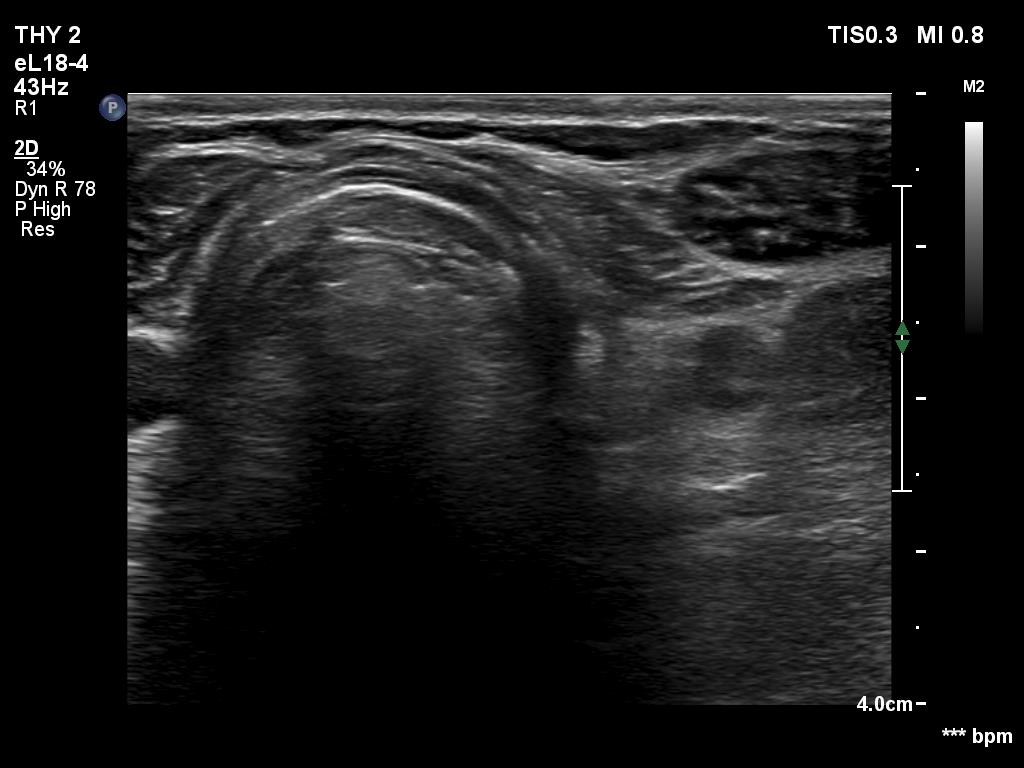

The operated thyroid - case 710

Five years after surgery (ultrasonographic picture 4)

Left lobe, another transverse scan.